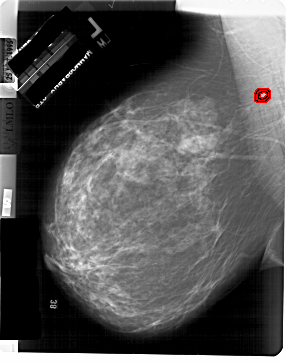

A_1899_1.LEFT_MLO

LEFT_MLO LINES 6871 PIXELS_PER_LINE 5431 BITS_PER_PIXEL 12 RESOLUTION 43.5 OVERLAY

FILE: A_1899_1.LEFT_MLO.OVERLAY

TOTAL_ABNORMALITIES 1

ABNORMALITY 1

LESION_TYPE MASS SHAPE IRREGULAR MARGINS SPICULATED

ASSESSMENT 5

SUBTLETY 4

PATHOLOGY MALIGNANT

TOTAL_OUTLINES 2